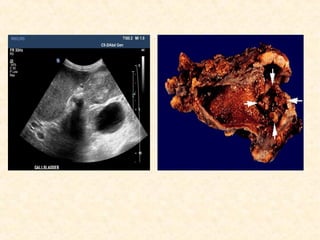

Diagnosis

• Ultrasonography

Diagnosis • FNAC /Biopsy(guided) • Ultrasonography • CT scan • Percutaneous transhepatic or endoscopic cholangiogram (in jaundiced pt) • MRCP